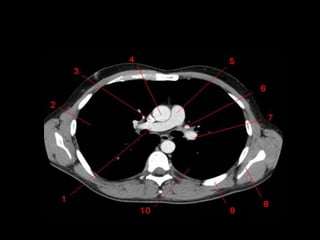

Mediastino Médio

• Pericárdio e seu conteúdo, arco aórtico e as

grandes artérias proximais, as artérias e veias

pulmonares centrais, traquéia, brônquios

principais e linfonodos.

• Nervo frênico e vago não são visíveis a TC.

• Janela Aortopulmonar

– Tecido adiposo, linfonodos, ligamento arterial e

nervo laringeo recorrente.

Tronco Pulmonar e Janela Aortopulmonar

• Inferior ao

arco aórtico e

a Esquerda

da traquéia

• Medial:

Traquéia, BPE

esofago.

• Lateral:

Superficie

Pleural do

lobo superior

esquerdo.

Hilo Pulmonar

• Artéria Pulmonar Direita passa anterior ao brônquio

principal direito

• Artéria Pulmonar Esquerda passa superior ao brônquio

principal esquerdo.